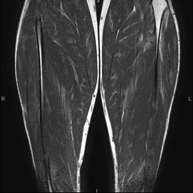

Exploració ideal per estudiar les lesions en músculs isquiotibials i quàdriceps, sovint lesionats en esportistes. També permet una bona valoració de tendons i de nervis perifèrics. La durada aproximada és de 20 minuts. No utilitza radiació ionitzan. - RM de Genoll

Prova diagnòstica no invasiva que consisteix en l'obtenció d'imatges d'alta definició anatòmica de la musculatura que s'estudia mitjançant l'ús d'un camp electromagnètic i ones de ràdio (amb un emissor i un receptor). No utilitza radiació ionitzant. Poques vegades requereix l'ús de contrast paramagnètic (Gadolini) per a una millor definició de les lesions. - RM d'Ossos i articulacions